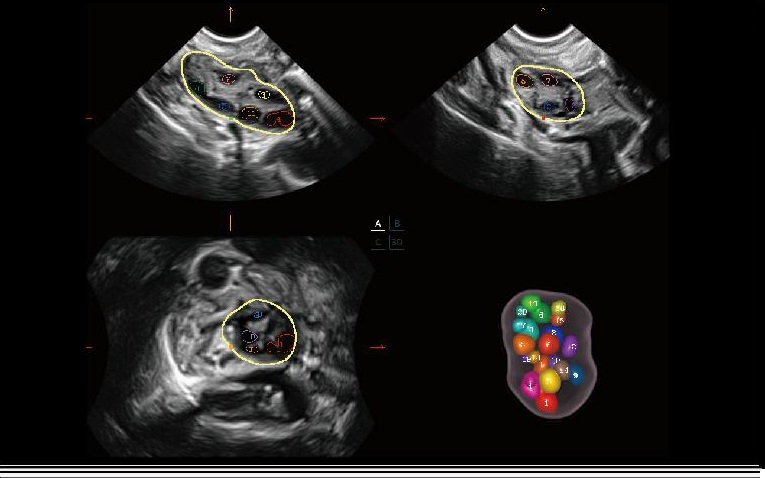

AVC Follicle

SonoAVC‑Follicle, foliküllerin sayılarını ve hacimlerini otomatik ve hızlı bir şekilde hesaplamayı sağlar.